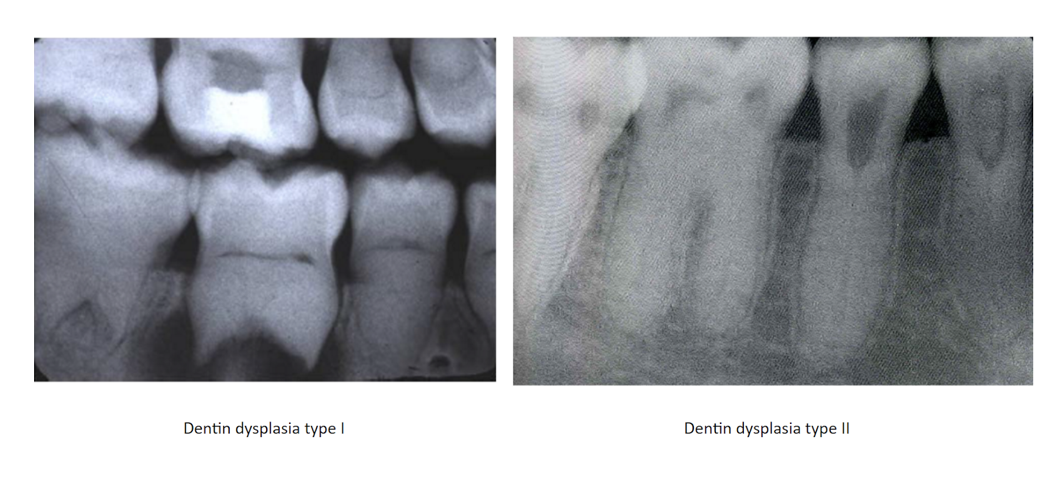

Dentin Dysplasia

Intrinsic alteration of dentin in permanent & primary teeth

Autosomal Dominant

2 types:

* Type 1: Chevron Pulp w/short roots

* Type 2: Thistle shaped Pulp w/normal roots; Primary teeth=blue or amber color

Tx: Not good candidates for restorations

* abnormal dental and pulp morphology

Type 1(radicular): Chevron pulp, minimal root development

Type 2: (Coronal): Thistle tube shaped pulps, normal root

* primary teeth= bluee/amber discoloration

Tx: Endo to keep primary teeth